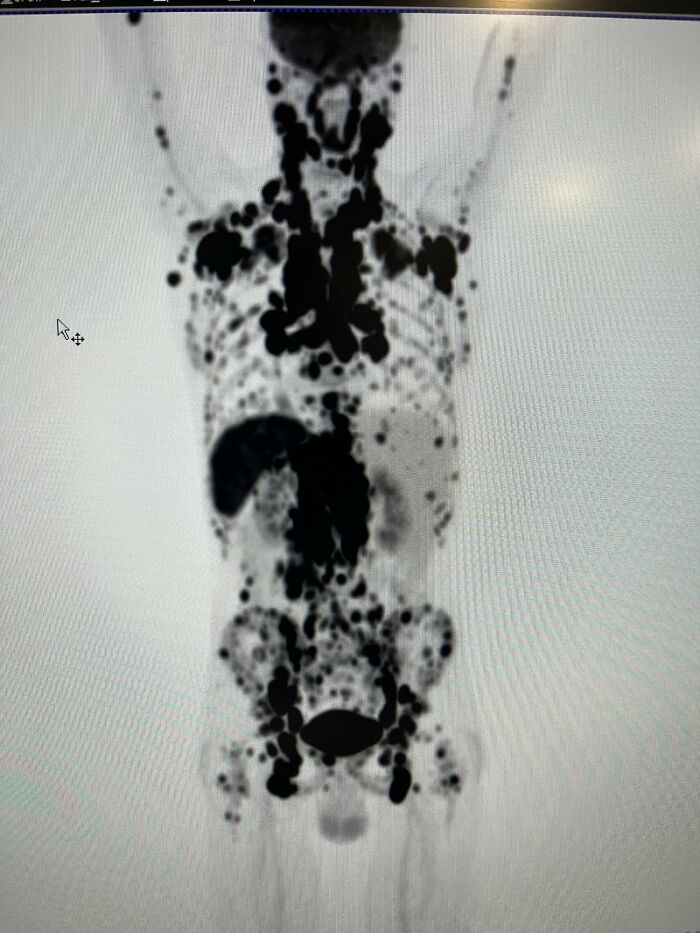

PET scans sound straight out of scifi.

We inject a specific radioactive tracer into your body. The isotope emits positrons (literal antimatter) as it decays. The positrons interact with electrons in your body and annihilate creating gamma ray bursts and we are able to track that light/energy to create a detailed 3D map of your body.

We use antimatter everyday to help save lives.

Image source: ProjectCoast, reddit